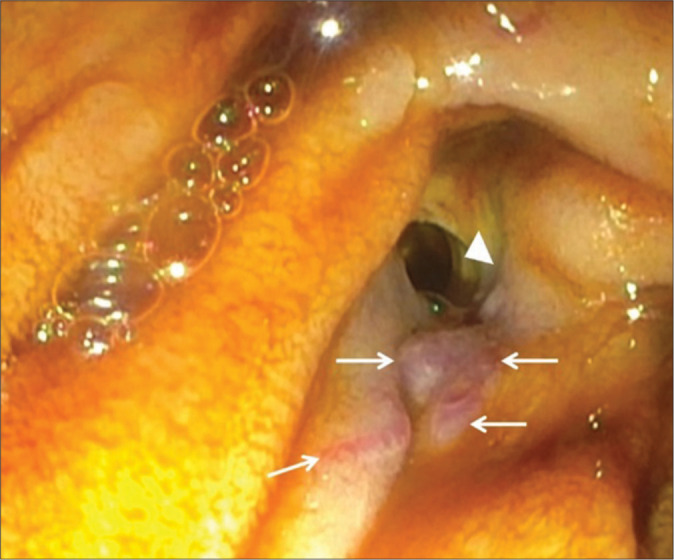

绝大多数因危重消化道出血(GIB)而入住重症监护室(ICU)的患者都有可预测的病因。一旦出血部位被定位在上消化道或下消化道,通常遇到的病因就非常有限。在极少数情况下,需要重症监护病房治疗的 GIB 的病因并非标准考虑因素之一,这可能会导致诊断和治疗延误。在很短的时间内,我们医院的内科重症监护室就收治了三名患者,每名患者的 GIB 病因都出乎意料。这三个病例都产生了各种具有启发性的图像,本系列文章将用这些图像来说明这些病症以及放射科在其评估和管理中的作用。

The great majority of patients admitted to the intensive care unit (ICU) for critical gastrointestinal bleeding (GIB) will have a predictable etiology. Once the site is localized to the upper versus the lower gastrointestinal tract, the number of typically encountered etiological possibilities is quite limited. On rare occasions, the cause of GIB requiring ICU care is not one of the standard considerations, potentially leading to diagnostic and therapeutic delays. Within a short time period, three patients were admitted to our institution's medical ICU each with a different unexpected cause of GIB. All three cases generated a variety of instructive images, which are used in the present series to illustrate these conditions and the role of radiology in their evaluation and management.